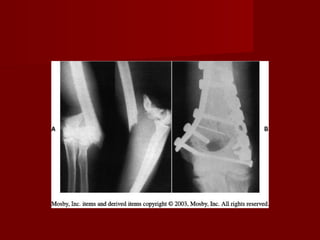

Fractura del tercio proximal del cúbito

con luxación de la cabeza radial

(fractura-luxación de Monteggia)

Clasificación de Bado en 4

tipos.

Mecanismo es por: golpe

directo en la cara cubital

del antebrazo o por caída

en      hiperpronación   e

hiperextensión.

Tratamiento consiste en la

reducción cerrada de la

luxación del radio y fijación

de la fractura del cubito.

Tratamiento      post-

operatorio:   a    las   2

semanas se retira férula y

puntos y se coloca yeso.

Durante la primeras 4-6

semanas el codo debe

mantenerse a 110 – 120

grados de flexión. A las 4

semanas se retira yeso y

el brazo se coloca en un

cuello-puño y se inicia

suave y progresivamente

movimientos             de

pronosupinación.

La extensión se autoriza

hasta las 6 semanas.